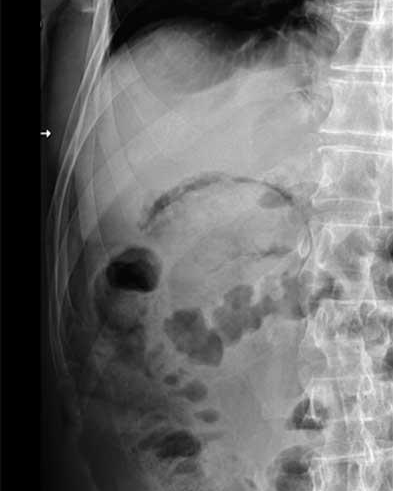

Sur le cliche de face ASP on peut en

voyait image de hydro-aerique et image de

l'air dans paroi de la vesicule biliaire . |

Image une cholecystite

emphysemateuse sur le cliche de face ASP . La

vesicule est distendue , paroi epais et image

hydroaerique de la region hypochondre droit . Cliche

ASP de face |